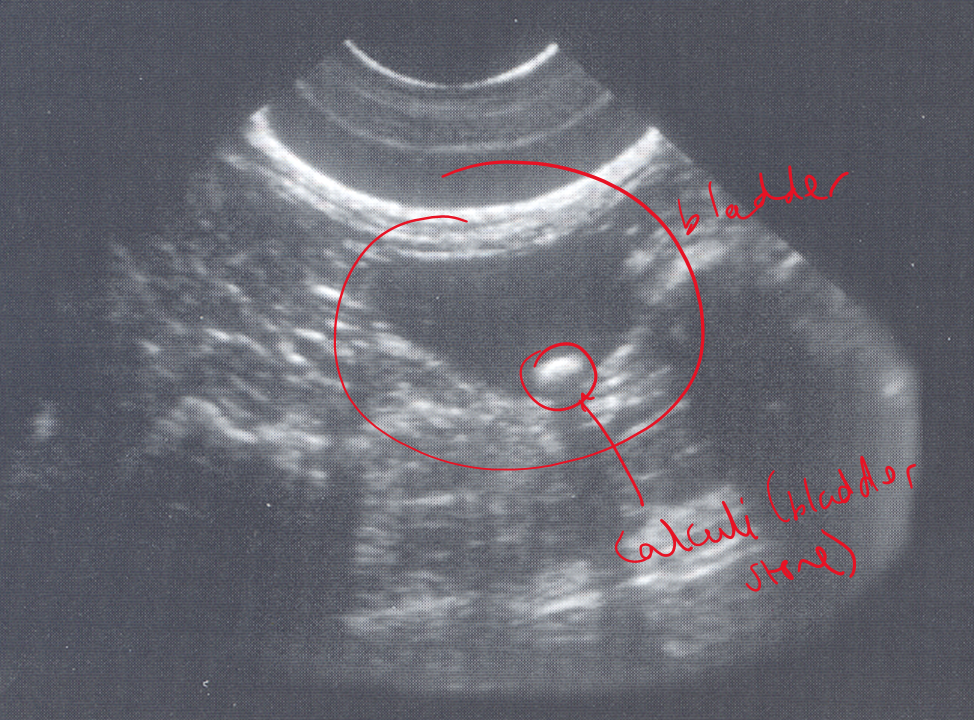

What is being shown in these bladders?

L —> thickened wall with a hyperechoic lesion arising from the wall —> consistent with a bladder wall mass

R —> thickened and within the lumen we can see hyperechoic areas which may be a mass or could be blood clots.